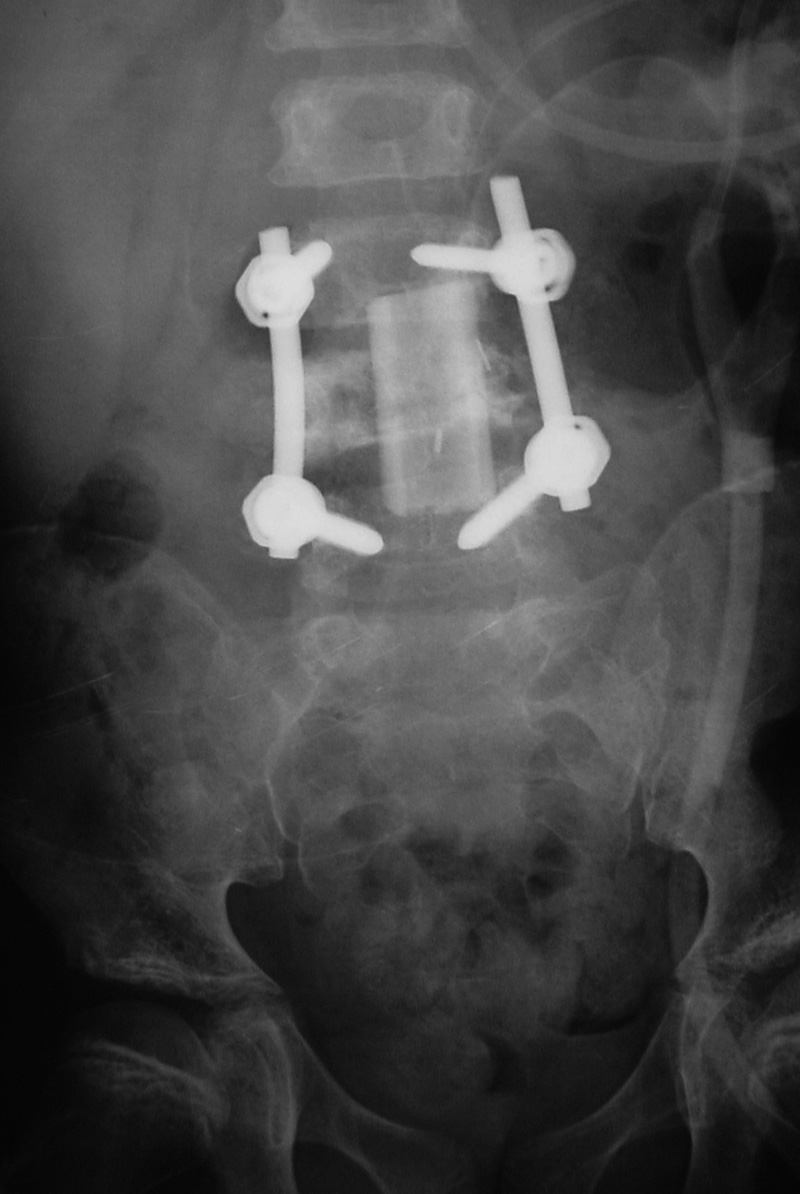

| Harms vertebral cage (AP view) |

| There is a vertebral cage and side plate and screws in the lower thoracic spine for treatment of a spinal tumor. From Hunter, 1994 |

| Vertebral corpectomy with vertebral cage and left lateral side plate |

|

| 70 year-old man with history of L1 and L3 injury and T11-L3 spinal fusion in the 1990's. Recent worsening of chronic lower back pain. Standard radiographs (left two images) show a vertebral body corpectomy cage at T12-L3 with placement of a left lateral side plate at the same levels. There are two proximal screws at T12, one of which enters the spinal canal as shown on subsequent CT (right two images). There are two distal screws at L3, the most distal of which enters the L3-4 disk space (lateral radiograph). |